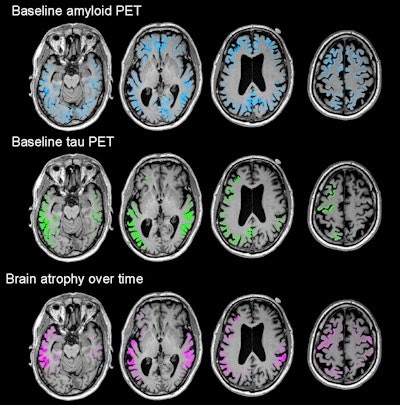

Images show four sequential cross sections of a single study participant's brain (left to right = bottom to top) to illustrate that the relationship between amyloid, tau, and future brain degeneration is similar across the brain, not just in the single cross sections shown in the other figures. Images courtesy of UCSF and Rabinovici et al.The researchers longitudinally charted a pattern of atrophy that was greatest in the temporoparietal, posterior cingulate, precuneus, and dorsal frontal areas. All of those areas of atrophy coincidentally matched significantly elevated levels of flortaucipir.

PiB-PET images revealed amyloid deposition in the prefrontal, posterior cingulate, and precuneus regions, as well as the lateral frontal and temporoparietal cortices. Flortaucipir-PET discovered maximum tau accumulation in the temporoparietal junction, the posterior cingulate, and the precuneus and moderate amounts in the dorsal frontal, occipital, and inferomedial temporal cortices.

Most importantly, those areas of tau buildup predicted subsequent atrophy in the same locations with more than 40% accuracy. Baseline PiB-PET scans, which detected amyloid, correctly predicted only 3% of future brain degeneration.